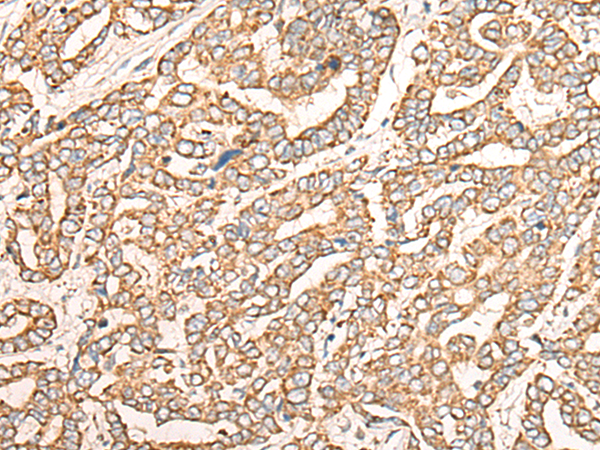

IHC positive control: |

Human liver cancer |